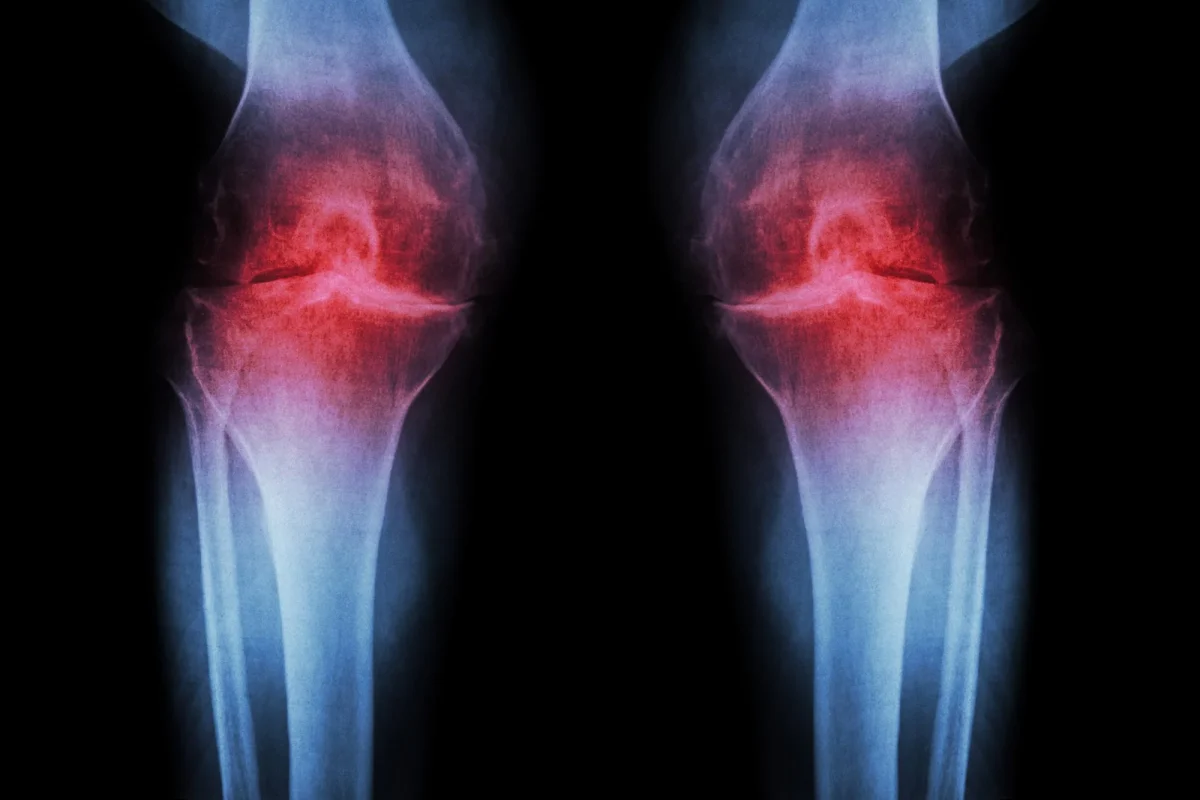

Μια εκτενής μελέτη που διήρκεσε επτά έτη αποκαλύπτει ότι η ρευματοειδής αρθρίτιδα (ΡΑ) δεν εμφανίζεται ξαφνικά τη στιγμή που αρχίζουν οι πόνοι στις αρθρώσεις. Αντίθετα, φαίνεται ότι η ασθένεια ξεκινά πολύ νωρίτερα, με αλλαγές στο ανοσοποιητικό σύστημα που εξελίσσονται «σιωπηλά» για χρόνια.